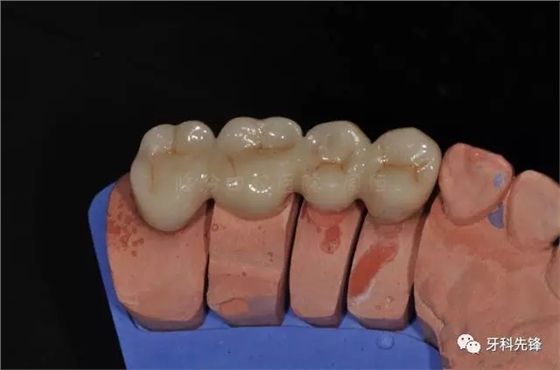

圖13牙體預(yù)備模型照

640.webp (17).jpg